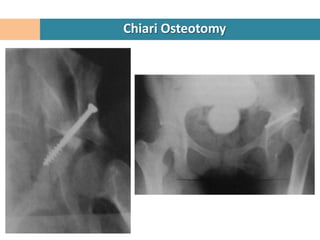

Chiari Osteotomy

Used when other procedures cannot

achieve a concentric reduction of hip.

Controlled fracture through ilium with

medial displacement of acetabular

fragment and the intact hip capsule

under the ilium.

Over time the hip capsule converts into

fibrocartilage and becomes the new

acetabular coverage.

A Salvage surgery